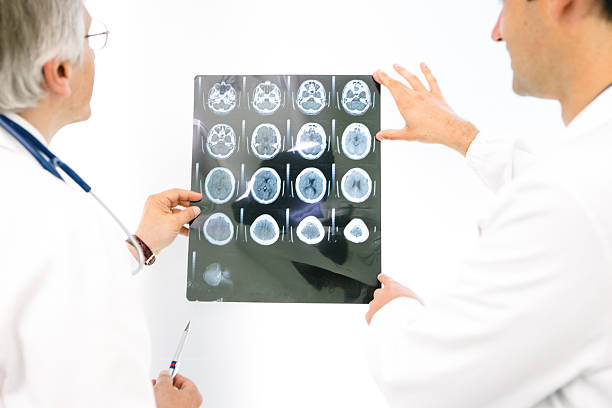

뇌출혈 전조증상 자세히 알아보기

뇌출혈은 두 개 내에 출혈이 있어 생기는 모든 변화를 말하는 것으로 가장 큰 원인으로는 고혈압 증상을 지목하곤 합니다. 고혈압은 산소와 영양소가 뇌로 들어가는 통로인 혈관에서 변화를 일으키기 때문인데 뇌동맥류가 손상된 경우에도 발생할 수 있으며 잦은 흡연이나 음주 등 여러 원인으로 합병증으로 인해 발생할 수 있습니다. 특히, 뇌출혈 증상 발생시 가능한 빨리 병원으로 가야하고 약 2시간 안에 응급처치를 받아야 하는데 이는 응급처치를 받지 않으면 바로 뇌 손상으로 사망에 이를 수 있기 때문에 이번 시간에는 뇌출혈 전조증상에 대해 정리해 보겠습니다.